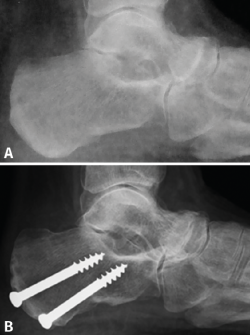

Introducción y objetivos: la enfermedad de Müller-Weiss (EMW) es una patología causada por la displasia del navicular que, en muchos casos, está mal o infradiagnosticada. Se presenta como un “pie plano-varo paradójico” y una artropatía talonavicular. En este trabajo pretendemos explicar nuestra experiencia con una cirugía de preservación articular –osteotomía “supervalguizante” de calcáneo aislada (de tipo Dwyer con desplazamiento lateral)– en nuestra primera serie de pacientes a los que no se realizó una artrodesis.

Material y métodos: estudio descriptivo retrospectivo de una serie de 17 casos de EMW en 15 pacientes operados en nuestra Unidad de Pie y Tobillo (2007-2015). Analizamos diferentes parámetros a través de la historia clínica, la exploración física, el estudio radiológico y escalas de valoración estandarizadas (escala visual analógica –EVA–, American Orthopaedic Foot and Ankle Society –AOFAS– y Likert).

Resultados: todos los pacientes tenían un varo subtalar y el 88,2% una fórmula metatarsal index minus. Existió una mejoría en todas las escalas de valoración utilizadas y en los parámetros radiológicos estudiados (cobertura talonavicular y clasificación de Maceira) en la mayoría de los pacientes. No se registraron complicaciones importantes. Un paciente no mejoró y precisó de una artrodesis a los 4 años de la osteotomía.

Conclusiones: la EMW produce un pie plano paradójico. La corrección quirúrgica del varo subtalar permite una mejoría clínica y radiológica notable. La osteotomía “supervalguizante” es una técnica sencilla y se ha constituido en nuestra técnica de elección, independientemente del estadio radiológico. La artrodesis de la columna medial ha quedado como técnica de rescate para fracasos de la cirugía de preservación articular.

Introduction and objectives: Müller-Weiss disease (MWD), a tarsal navicular dysplasia, is often misdiagnosed or underdiagnosed. Clinical presentation as a paradoxical “flatfoot varus” combines with arthritic talonavicular changes. In the present study we show our experience with a joint-preserving surgical treatment –isolated “super-lateral-slide osteotomy”– in the first series of patients in which a tarsal arthrodesis was not performed.

Material and methods: we present a descriptive, retrospective study of a series of 17 MWD cases in 15 patients that underwent surgery in our Orthopaedic Foot and Ankle Unit (2007-2015). We analyze different parameters through the clinical history, physical examination, complementary tests and standardized evaluation scales (visual analogue scale –VAS–, American Orthopaedic Foot and Ankle Society –AOFAS–, and Likert).

Results: all patients presented with subtalar varus and 88.2% had a metatarsal index minus formula. There was an improvement in all scales studied. Radiographic parameters also improved in all cases (talonavicular coverage, Maceira classification). Most patients had considerable pain relief and just one did not improve and required an arthrodesis four years after the osteotomy.

Conclusion: MWD presents with a paradoxical flatfoot varus. Surgical correction of hindfoot varus allows for a mechanical change that produces clinical and radiological improvement. An isolated “super-lateral-slide osteotomy” is an easy technique to achieve varus correction regardless the radiographic stage of the disease and has become our surgical procedure of choice. Medial column arthrodesis is left as a salvage procedure for those cases that do not improve with the osteotomy.